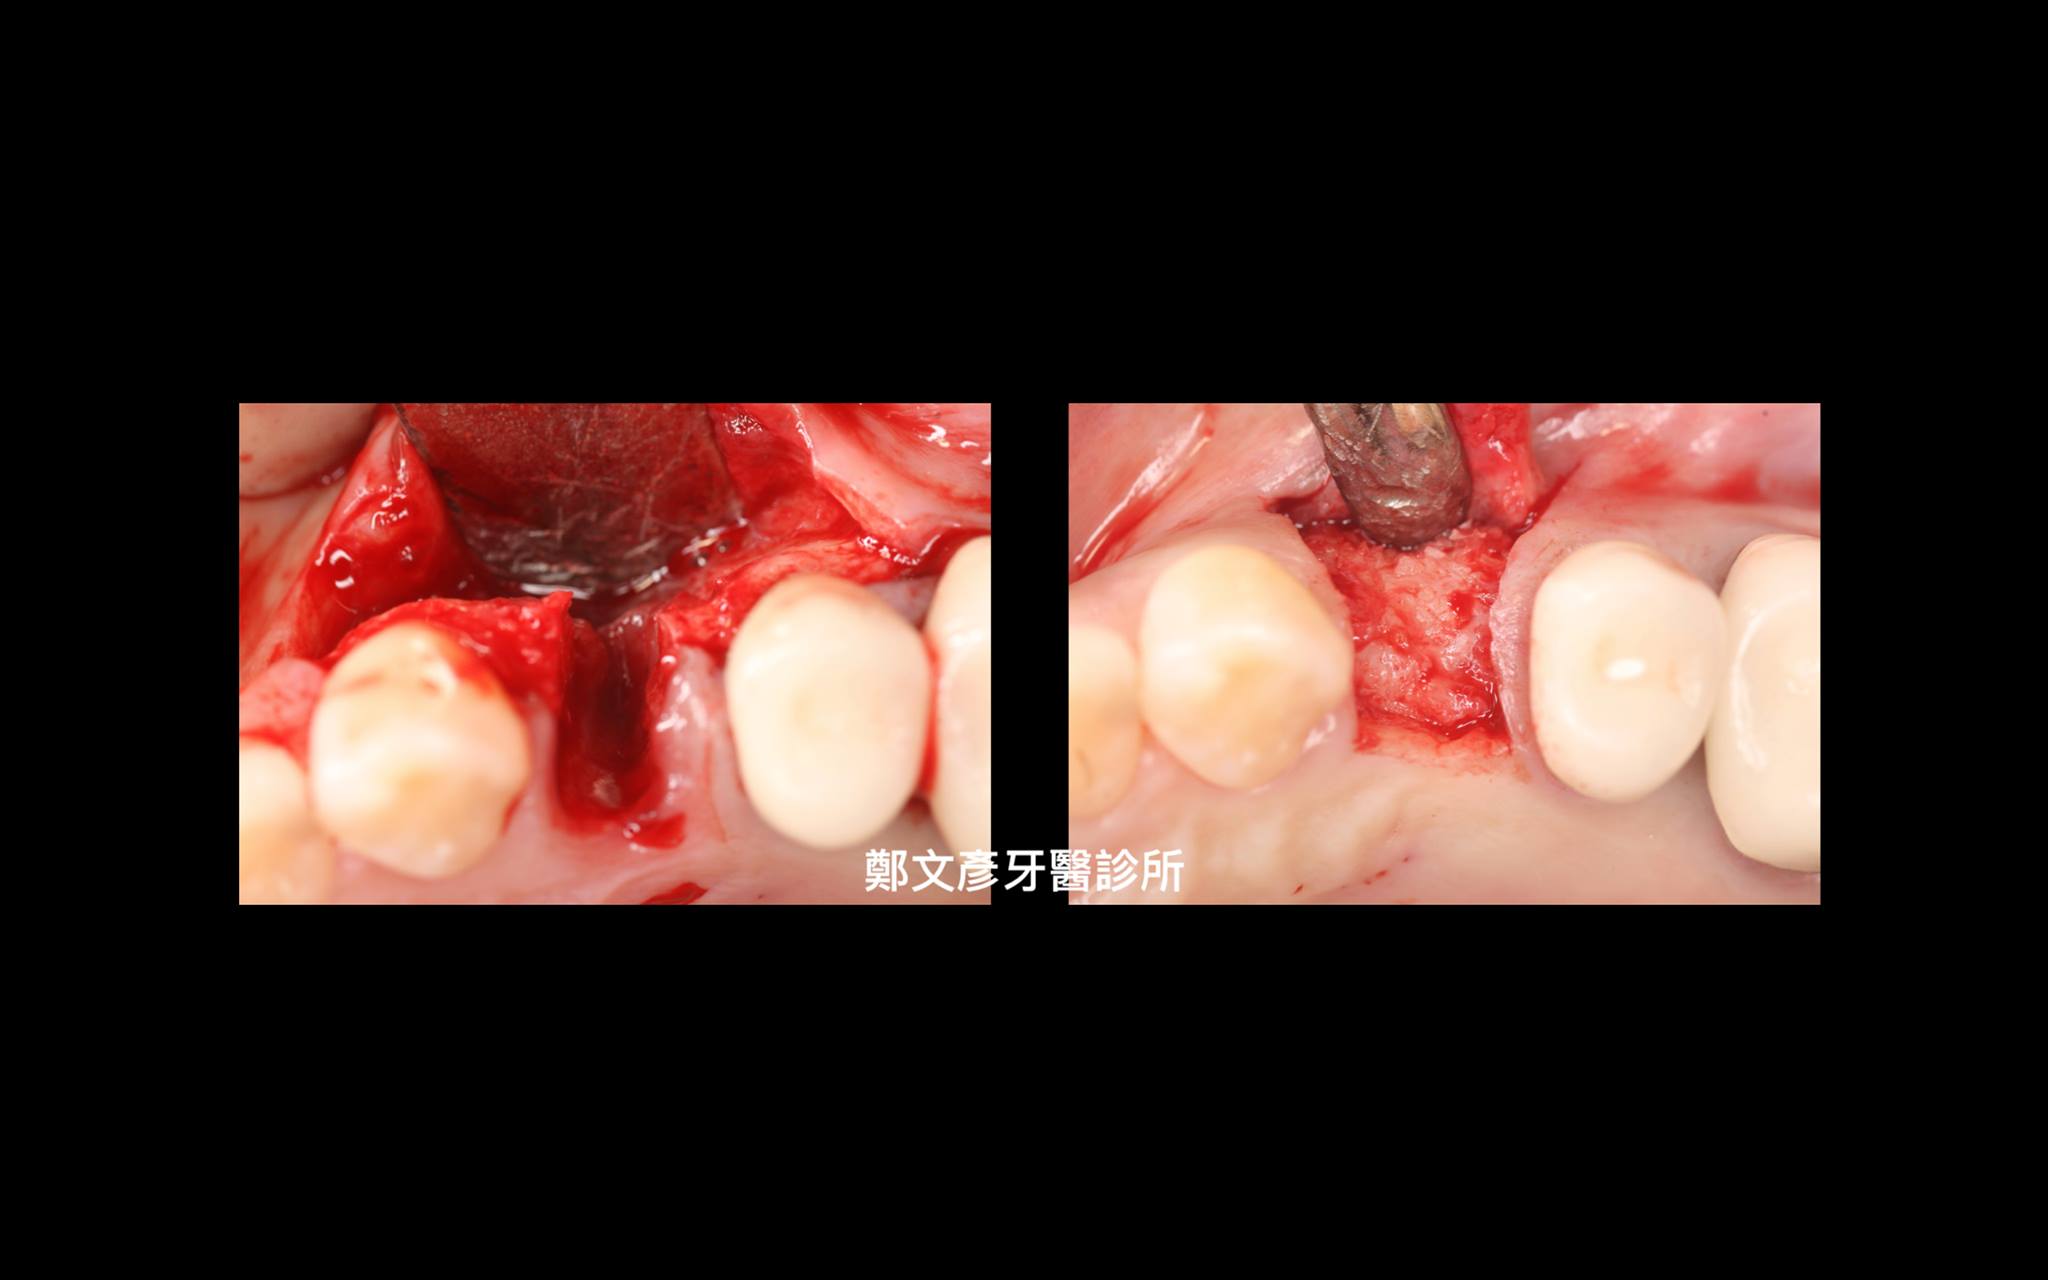

3. Role of granulation tissue in socket preservation

Role of granulation tissue in socket preservation